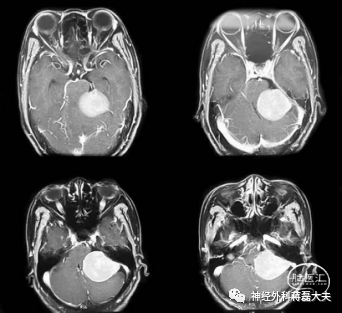

神经外科蒋磊教授带领团队充分讨论,患者术前喉镜示左侧声带运动麻痹,头颅MRI检查发现桥小脑角巨大肿瘤,紧邻脑干,与舌咽面神经、迷走神经等后组颅神经关系密切。蒋磊教授指出肿瘤体积巨大,但从影像学判断为良性脑膜瘤,直径6cm,已经明显压迫脑干颅神经导致吞咽困难、声音嘶哑和左侧声带麻痹,由于肿瘤巨大已经严重压迫脑干和小脑导致行走不稳,必须尽快手术,以防出现生命危险。

考虑到患者术前已经出现后组颅神经受损,手术更需仔细轻柔操作,最大程度保护颅神经、脑干和小脑功能。蒋磊主任与家属充分沟通,经家属同意,最终决定在神经电生理监测下行左侧乙状窦后入路开颅手术切除肿瘤。